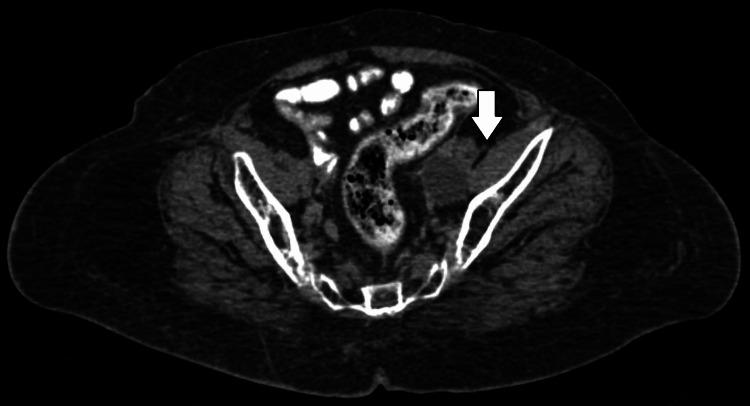

The case report details the adaptive radiotherapy management of a 75-year-old female diagnosed with high-grade endometrial carcinoma. The patient, who was known to be hypertensive with no other comorbidities and no family history of cancer, presented with a complaint of bleeding per vagina for six months. Following extensive investigations, she underwent a laparoscopic radical hysterectomy. Postoperative histopathology confirmed endometrial adenocarcinoma International Federation of Gynecology and Obstetrics (FIGO) stage IA, grade III. The adjuvant treatment plan included adjuvant chemoradiotherapy to the postoperative tumor bed and draining lymph nodes. On planning computed tomography (CT), the patient's lymphocele responded remarkably to radiation therapy, an unusual outcome that underscores the potential efficacy of adaptive radiotherapy in complex cases.

摘要

该病例报告详细介绍了一名75岁女性高级别子宫内膜癌的自适应放射治疗管理情况。该患者已知患有高血压,无其他合并症,且无癌症家族史,因阴道出血六个月前来就诊。经过广泛检查后,她接受了腹腔镜根治性子宫切除术。术后组织病理学证实为国际妇产科联盟(FIGO)IA期、III级子宫内膜腺癌。辅助治疗方案包括对术后肿瘤床和引流淋巴结进行辅助放化疗。在计划计算机断层扫描(CT)时,患者的淋巴囊肿对放射治疗反应显著,这一不寻常的结果突出了自适应放射治疗在复杂病例中的潜在疗效。